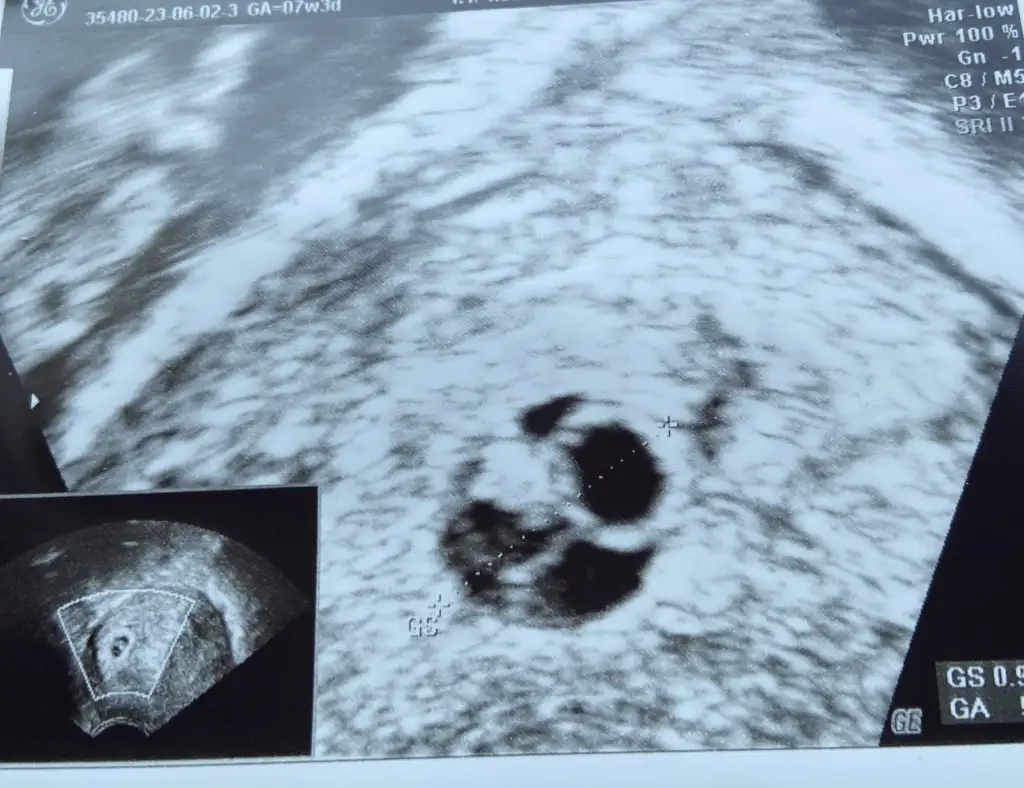

Selam kızlar geçen cuma gittiğimde sadece kese ve yolk vardı 4+6 demişti az önce gittim bebek 6+1 kese 5+0 dedi yanında boş kese var gibi bide dedi kese geçen haftaya göre büyümemiş yani ama kalp duyduk takip edecez dedi böyle olup devam edebilir mi acaba sağlıklı

Eklentiler

• IMG_8151.webp

IMG_8151.webp

44,8 KB · Görüntüleme: 71

• IMG_8150.webp

IMG_8150.webp

47,5 KB · Görüntüleme: 67

Evet ikinci fotoğrafta yüzük gibi olan yerde iki kese var dedi o büyümesini engelledi sanırım hayırlısı bakalım ya inşallah sende duyarsın kalbi